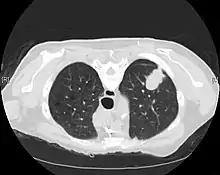

CT scan- adenocarcinoma of the left lung

The majority of lung cancers can be characterized as either small cell lung cancer (SCLC) or non-small cell lung cancer (NSCLC). Lung adenocarcinoma is one of the three major subtypes of NSCLC, which also include squamous carcinoma and large cell carcinoma.[15]

Imaging

A chest x-ray (radiograph) is often the first imaging test performed when a person presents with cough or chest pain, particularly in the primary care setting. A chest radiograph may detect a lung nodule/mass that is suggestive of cancer, although sensitivity and specificity are limited.

CT imaging provides better evaluation of the lungs, with higher sensitivity and specificity for lung cancer compared to chest radiograph (although still significant false positive rate[27]). Computed tomography (CT) that is specifically aimed at evaluating lung cancer includes the chest and the upper abdomen. This allows for evaluation of other relevant anatomic structures such as nearby lymph nodes, adrenal glands, liver, and bones which may show evidence of metastatic spread of disease.[4] Indeed, the US Preventative Services Task Force recommends annual screening with low-dose CT in adults aged 55 to 80 years who have a 30 pack-year smoking history and currently smoke or have quit within the past 15 years, with certain caveats (see Lung cancer screening).[28]

Nuclear medicine imaging, such as PET/CT and bone scan, may also be helpful to diagnose and detect metastatic disease elsewhere in the body.[7] PET/CT uses a metabolically active tracer that allows clinicians to identify areas of the body that are hypermetabolic. Increased uptake of the tracer occurs in malignant cells and areas of inflammation or infection. Integrating the imaging reflective of metabolic activity with normal CT imaging allows for higher sensitivity and specificity compared to PET alone.[4]